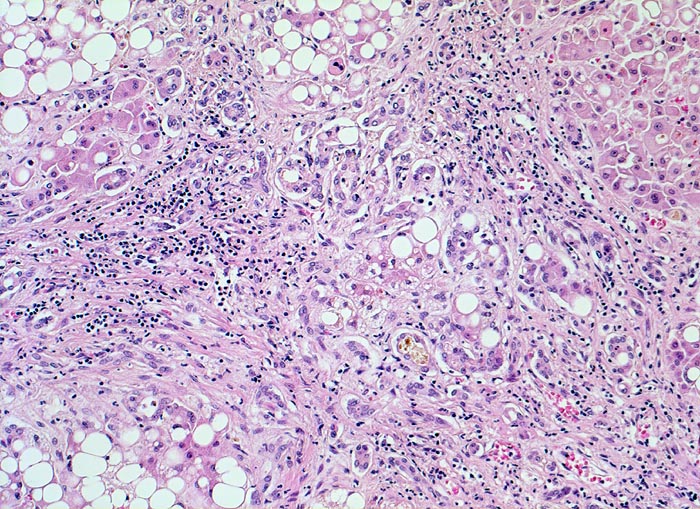

PathoPic – image database / PathoPic ID 4762 - alkoholische Leberzirrhose, Steatose, septische Cholestase

alkoholische Leberzirrhose, Steatose, septische Cholestase

Breite fibröse Bindegewebssepten mit lockerem gemischtem Entzündungsinfiltrat und Ductulusproliferation. Ein Ductulus ist dilatiert und enthält einen Gallepfropf. Die Hepatozyten enthalten grosse Fettvakuolen (grobtropfige Verfettung).

Eine Cholestase bei Sepsis, Hämolyse oder Schock involviert typischerweise die Ductuli und die Hering Kanäle in der Peripherie der Portalfelder. Die betroffenen Ductuli sind dilatiert und enthalten einen Gallepfropf. Zusätzlich besteht oft eine Cholestase in der Läppchenperipherie.